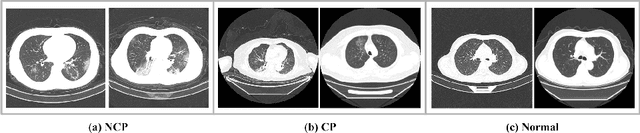

Abstract:Early detection of the coronavirus disease 2019 (COVID-19) helps to treat patients timely and increase the cure rate, thus further suppressing the spread of the disease. In this study, we propose a novel deep learning based detection and similar case recommendation network to help control the epidemic. Our proposed network contains two stages: the first one is a lung region segmentation step and is used to exclude irrelevant factors, and the second is a detection and recommendation stage. Under this framework, in the second stage, we develop a dual-children network (DuCN) based on a pre-trained ResNet-18 to simultaneously realize the disease diagnosis and similar case recommendation. Besides, we employ triplet loss and intrapulmonary distance maps to assist the detection, which helps incorporate tiny differences between two images and is conducive to improving the diagnostic accuracy. For each confirmed COVID-19 case, we give similar cases to provide radiologists with diagnosis and treatment references. We conduct experiments on a large publicly available dataset (CC-CCII) and compare the proposed model with state-of-the-art COVID-19 detection methods. The results show that our proposed model achieves a promising clinical performance.